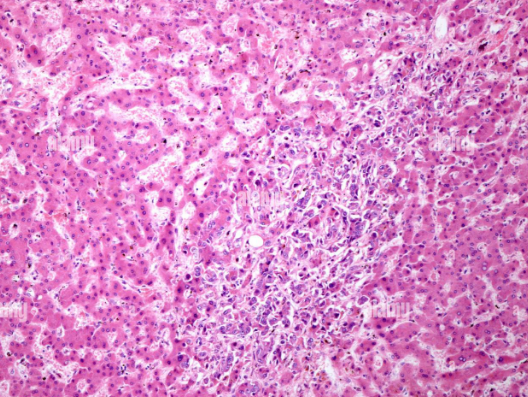

담관암은 간에서 생성된 담즙을 십이지장으로 운반하는 담관에서 발생하는 악성 종양이다. 발병률은 전체 암 중에서 높지 않지만, 조기 발견이 어렵고 진행 속도가 빠른 데다 수술 외에는 뚜렷한 치료법이 부족하다는 점에서 예후가 좋지 않은 암으로 꼽힌다. 미국에서는 매년 약 2만 3천 명이 담관암 진단을 받는데, 이 중 85% 이상이 2차 치료제 부재로 인해 화학항암제 조합에 의존하고 있다. 문제는 이런 화학항암제의 객관적 반응률(ORR)이 5% 수준에 그친다는 점이다. 종양 크기 감소나 치료 효과를 기대하기 어려운 상황에서 환자와 의료진 모두 대안을 갈구해왔다.

ABL001은 바로 이런 미충족 의료 수요를 겨냥한 약물이다. 에이비엘바이오가 개발한 이 표적 이중항체는 암 조직 내 신생혈관 생성을 억제하고, 이를 통해 암세포를 사멸시키는 기전을 갖췄다. 단순히 증상을 완화하는 데 그치지 않고, 근본적인 종양 억제 효과를 목표로 한다는 점에서 기존 치료제와 차별화된다.